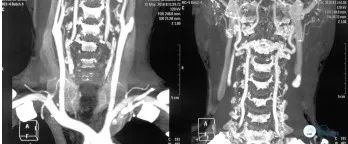

头颈CTA(2018-05-16):左侧颈内动脉闭塞(图2)

头部CTA(2018-06-08):左侧颈内动脉未见显示,走行区可见多发钙化;右侧颈内动脉岩骨段、海绵窦段管壁可见钙化,管腔多发狭窄。右侧大脑前动脉水平段纤细。左侧大脑中动脉显示纤细。左侧后交通动脉未见明确显示(图3)